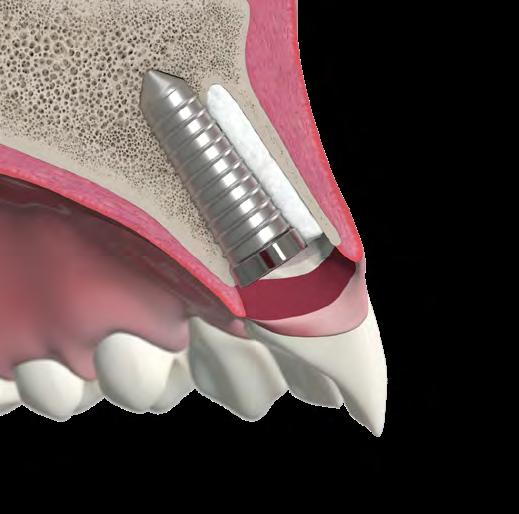

3D implant placement (using a surgical guide)

• Good bone availability for palatal wall implant positioning

Use of a narrow or regular diameter implant

• Achieve primary stability and maintain a buccal gap >2 mm